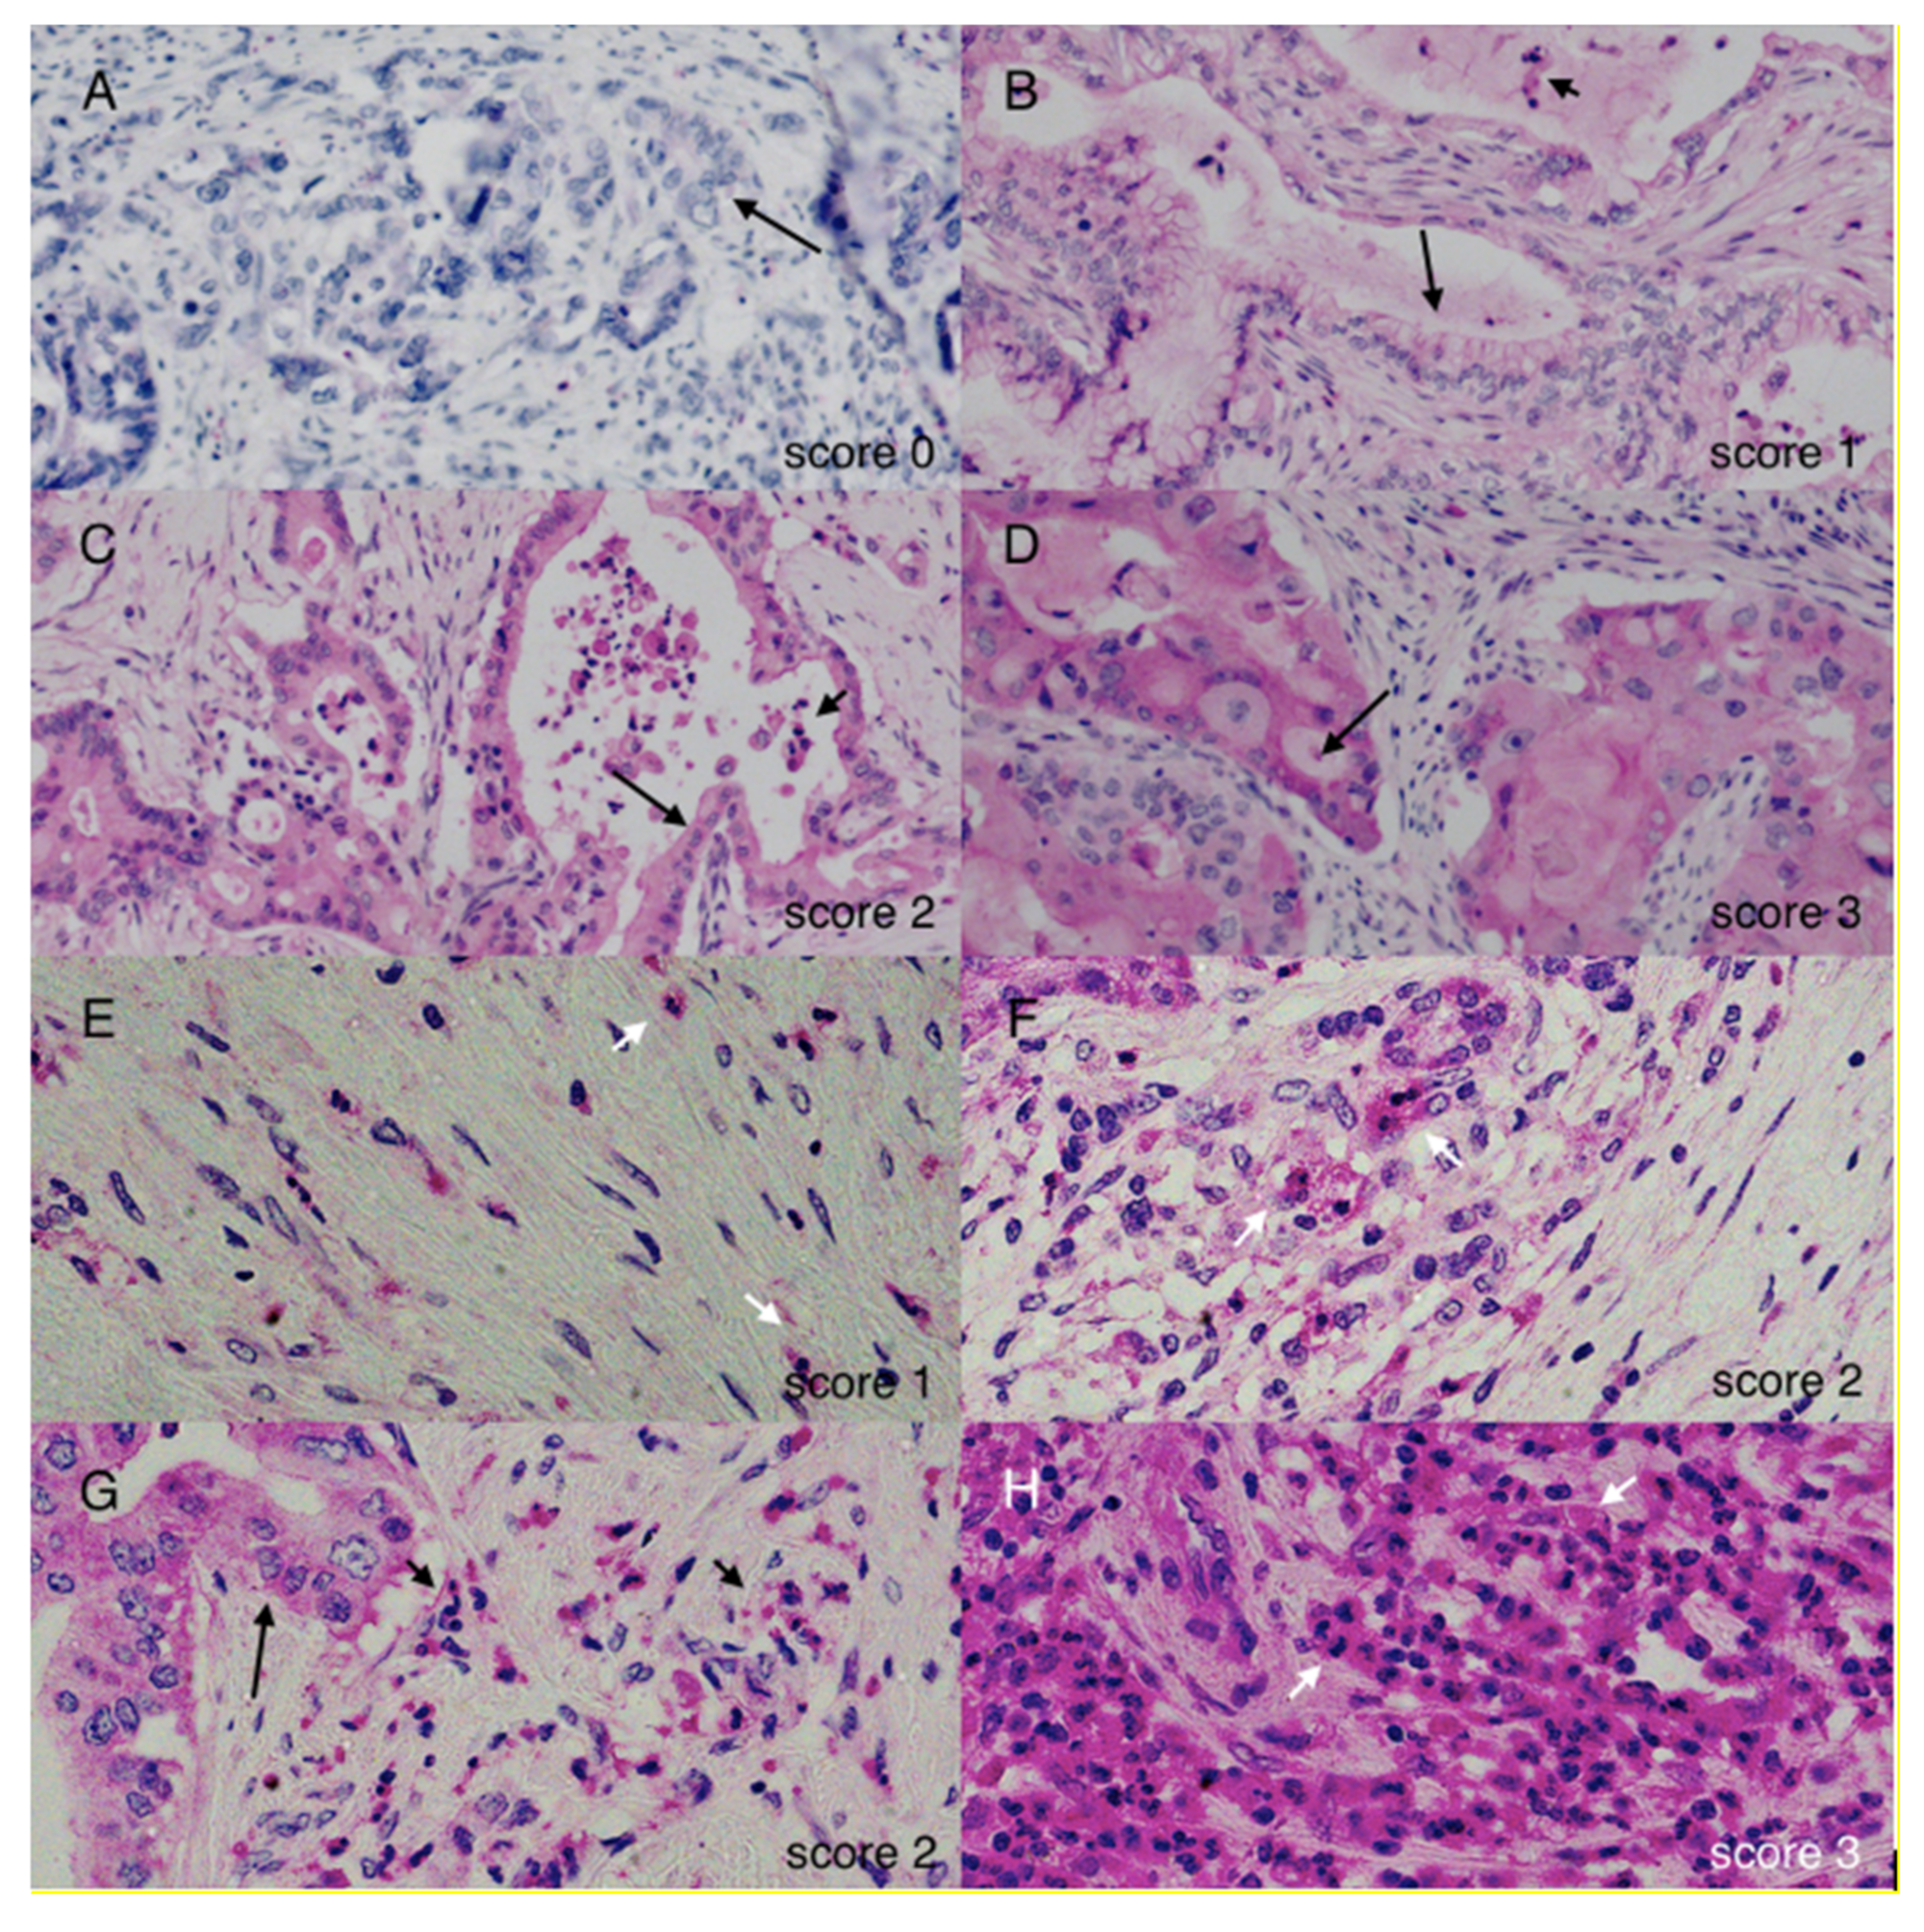

4.3. Evaluation of Stainings